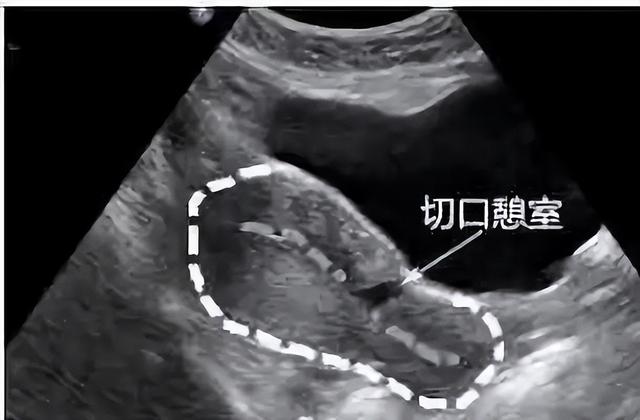

对于手术,我们老百姓有个俗称,叫「开刀」。既然是开刀自然会有一个切口,当剖宫产术后的子宫切口愈合缺陷时,切口处会出现一个与宫腔相通的凹陷,看起来好像一道沟,这个凹陷就是我们所说的憩室。

剖宫产术后子宫切口憩室 (preꦿvious cesareanscar defect,PCSD )以往报道较少 ,1955 ♛年西班牙学者首次报道了子宫切口憩室。由于它是在剖宫产后出现,所以被称为剖宫产术后子宫切口憩室,又俗称为剖宫产瘢痕憩室。

子宫切口憩室多位于子宫下段或峡部,少数位于宫颈上段,主要与原剖宫产切口部位及剖宫产时临♌床宫颈有无缩短或扩展有🅰关,简单点说,它就像一间违章改建的“危房”。